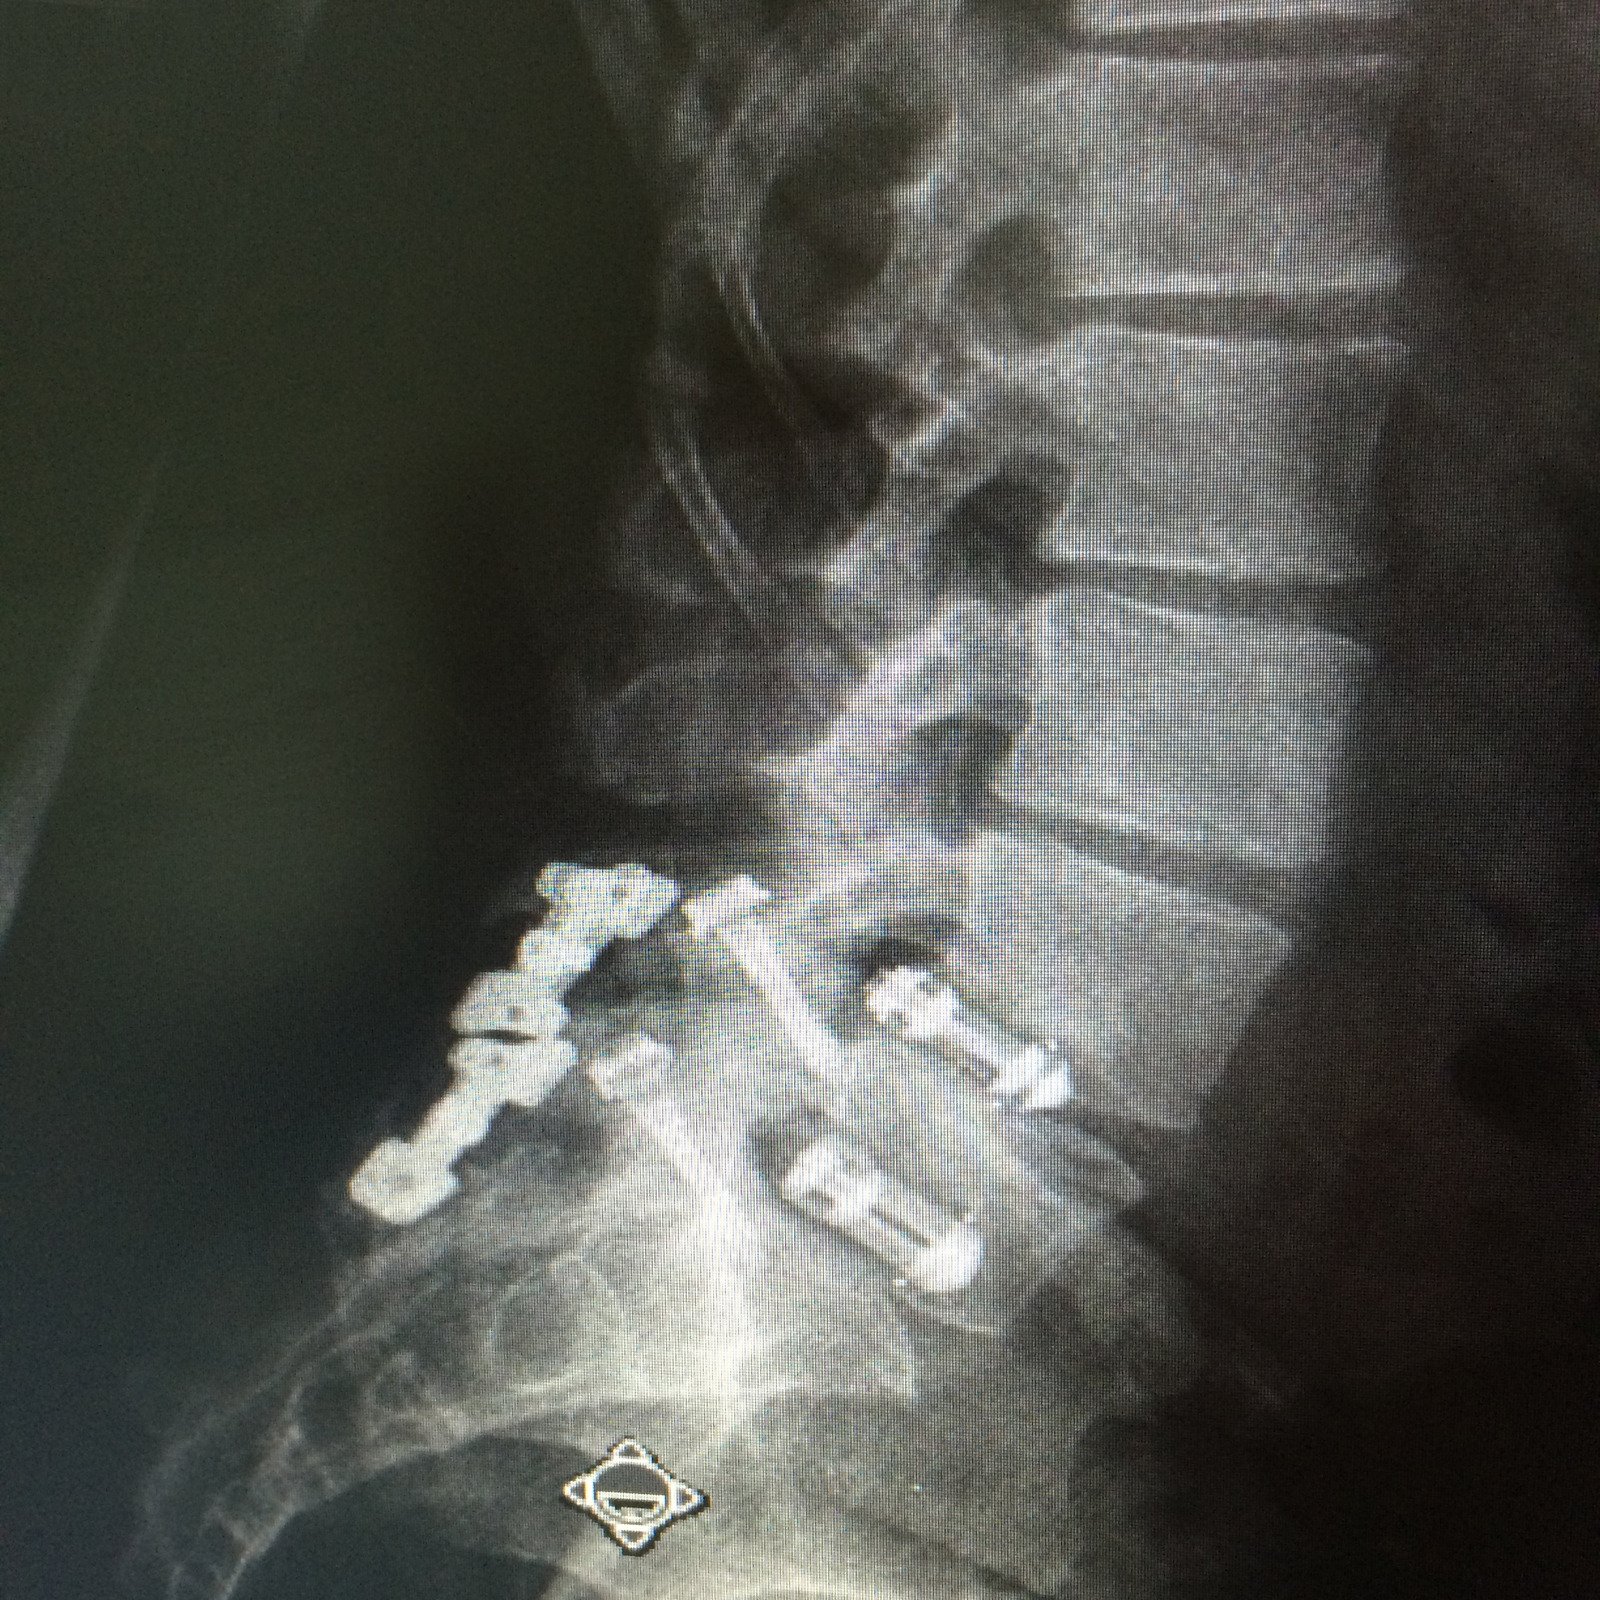

케이지 삽입: 디스크 공간에 유합 케이지를 삽입하고, 이를 통해 두 인접한 척추체를 유합합니다.

DLIF는 척추의 측면에서 접근하여 디스크와 인접한 척추체를 유합하는 수술입니다.

전통적인 후방 접근법과 달리, DLIF는 측면 접근법을 사용하여 주요 근육과 신경을 피할 수 있어 최소 침습 수술로 간주됩니다.

이 방법은 디스크 탈출증, 척추관 협착증, 척추 불안정성 등 다양한 요추 질환을 치료하는 데 사용됩니다.